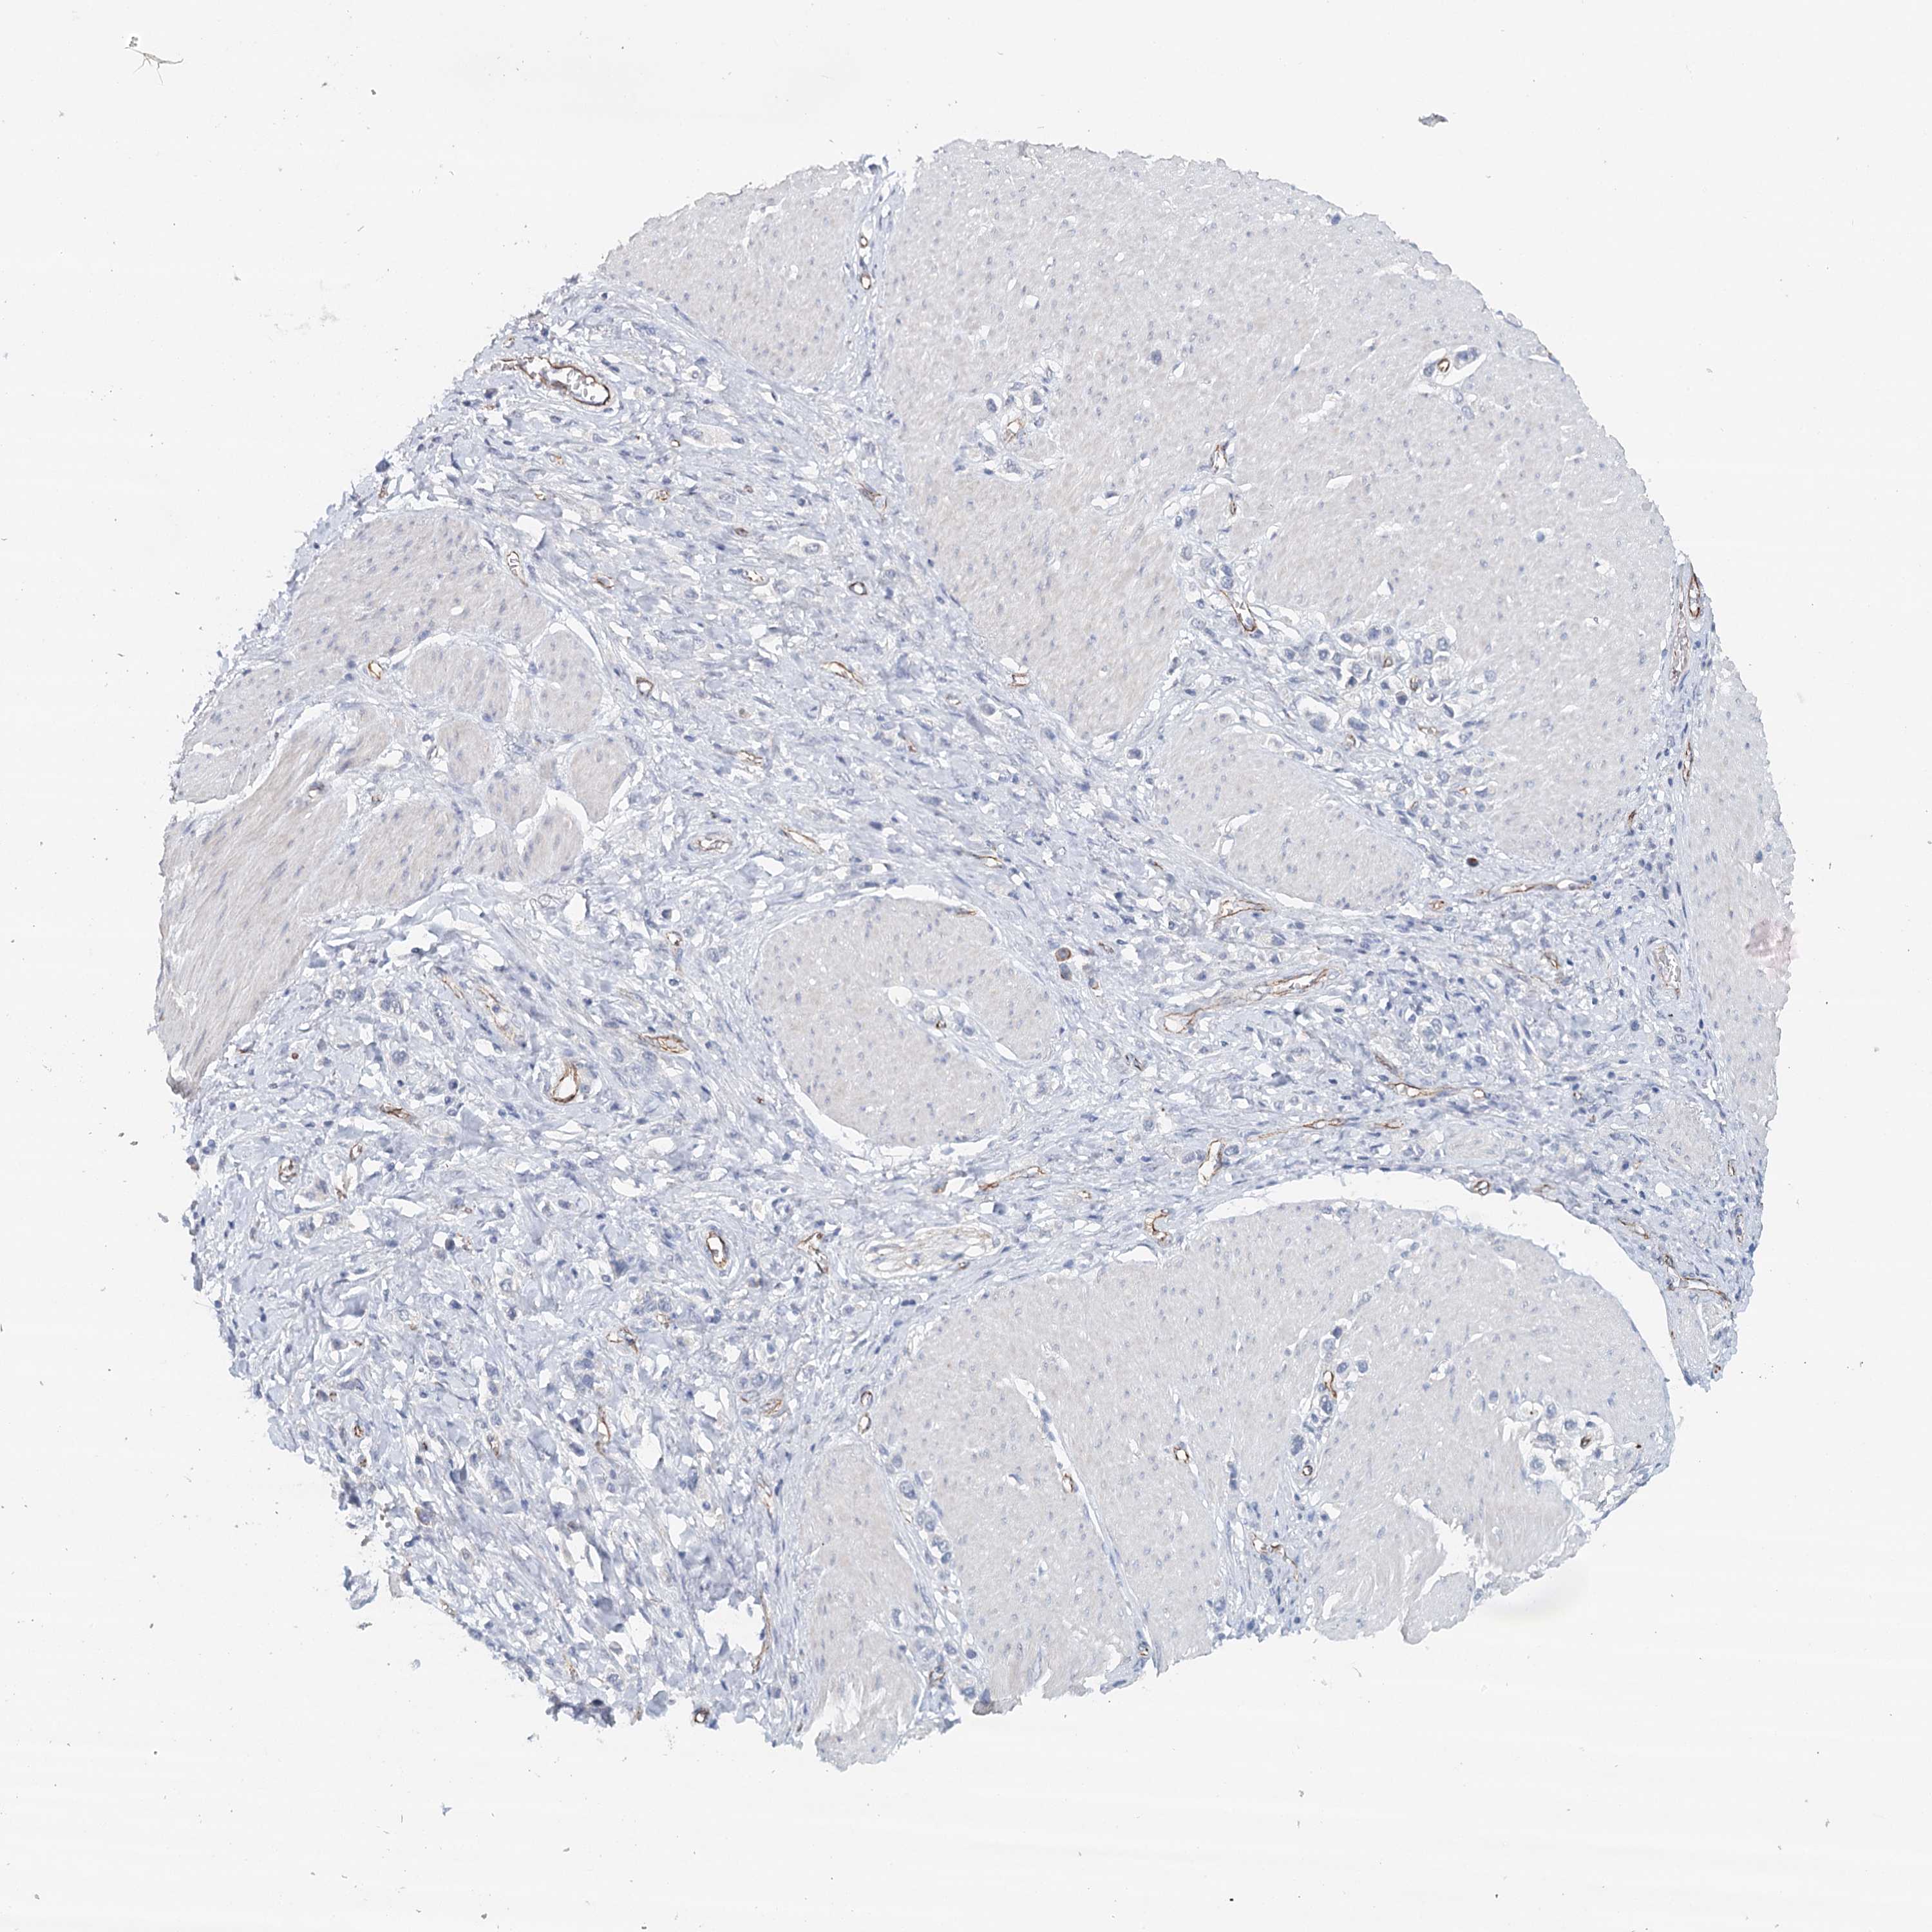

STOMACH CANCER - Protein expressioni

A mouse-over function shows sample information and annotation data. Click on an image to view it in a full screen mode. Samples can be filtered based on level of antibody staining by selecting one or several of the following categories: high, medium, low and not detected. The assay and annotation is described here.

Note that samples used for immunohistochemistry by the Human Protein Atlas do not correspond to samples in the TCGA dataset.

Antibody stainingi

Antibody staining in the annotated cell types in the current human tissue is reported as not detected, low, medium, or high, based on conventional immunohistochemistry profiling in selected tissues. This score is based on the combination of the staining intensity and fraction of stained cells.

Each image is clickable and will lead to virtual microscopy that enables deeper exploration of all samples and also displays staining intensity scores, fraction scores and subcellular localization as well as patient and tissue information for each sample.

Antibody HPA034631

Antibody HPA071347

Antibody CAB033265

Antibody CAB037325

Staining

High

Medium

Low

Not detected

Intensity

Strong

Moderate

Weak

Negative

Quantity

>75%

75%-25%

<25%

None

Location

Nuclear

Cytoplasmic/membranous

Cytoplasmic/membranous,nuclear

Adenocarcinoma, NOS

Adenocarcinoma, High grade